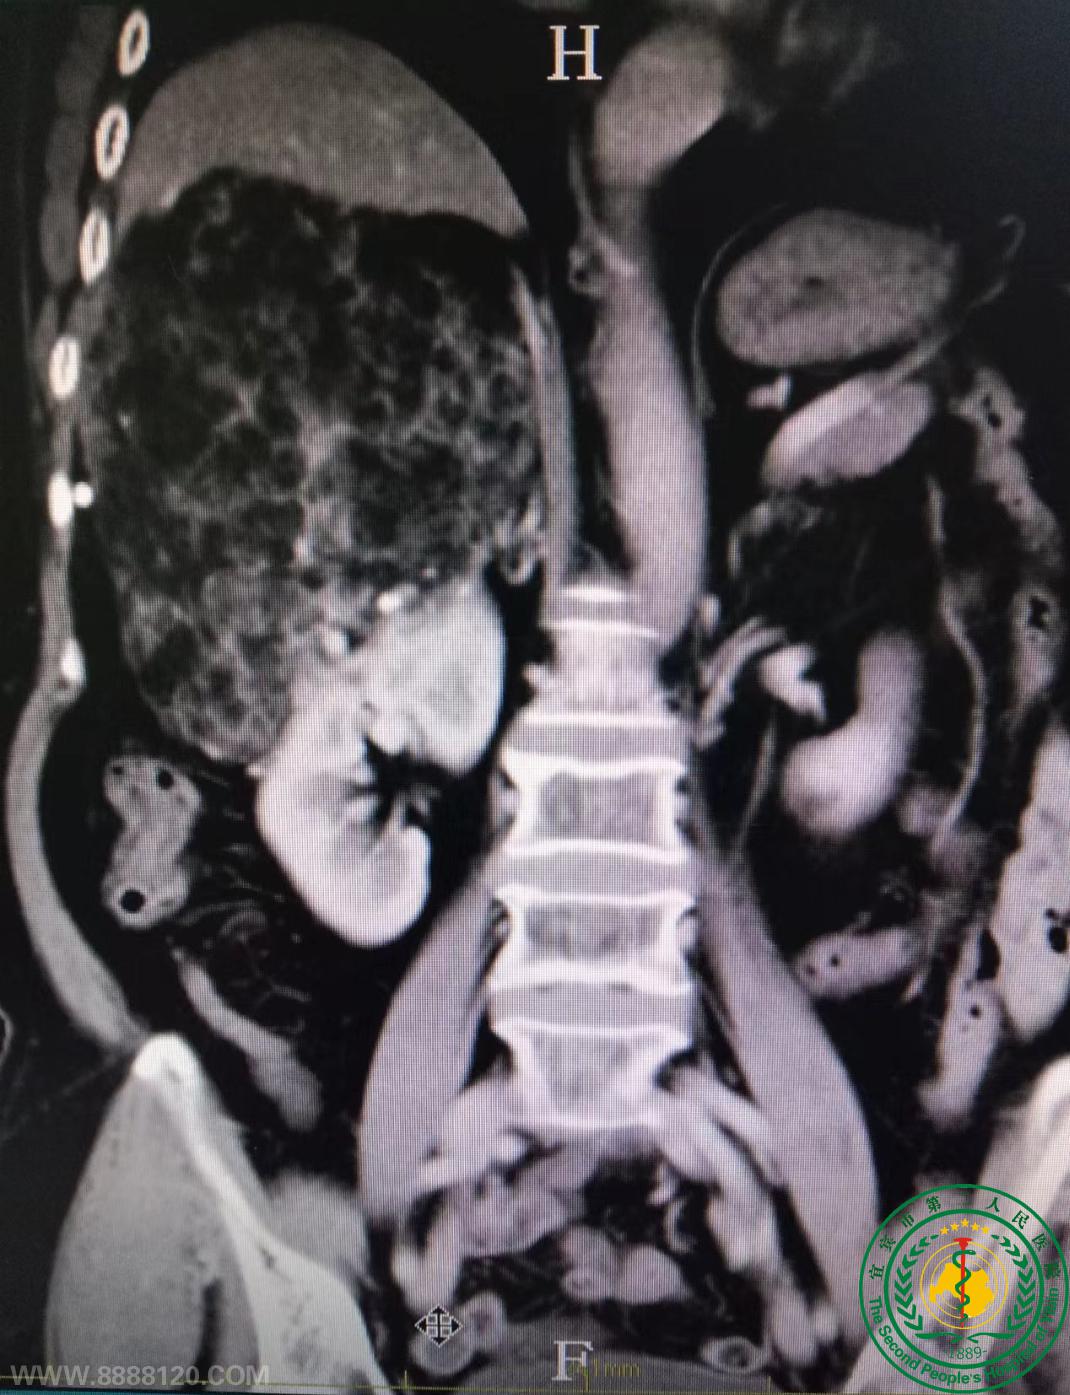

宜宾市第二人民医院泌尿外科顺利完成一例高难度肾部份切除术

宜宾市第二人民医院泌尿外科顺利完成一例高难度肾部份切除术  43770